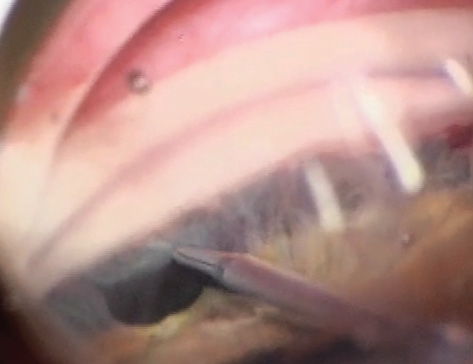

4. 전방각 유착해리술 Goniosynechialysis

급성 폐쇄각 녹내장 발작이 수차례 반복된 경우,

수술이나 외상등에 의해서 발생한

주변부 홍채유착(Peripheral anterior synechia, PAS)이 180도 이상 걸쳐있는 경우에는

수술적으로 전방각을 막고 있는 주변부 홍채를 떼어낼수 있습니다.

이를 전방각 유착해리술, Goniosynechialysis 라고 합니다.

대부분은 백내장 수술을 시행하면서 같이 시행하게되고,

전방각경이 있으면, 전방각경으로 전방을 직접 관찰하면서 시행해야 조직손상으로 인한 출혈을 최소화 할수 있습니다.